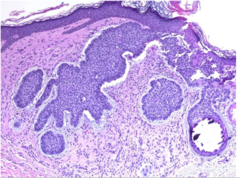

Seborrheic Keratosis

Front

What is the name of this epithelial tumor

Back